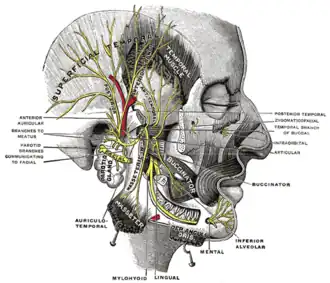

A number of different structures pass through the gland. From lateral to medial, these are:

- Facial nerve

- Retromandibular vein

- External carotid artery

- Superficial temporal artery

- Branches of the great auricular nerve

- Maxillary artery

The facial nerve (CN VII) splits into its branches within the parotid gland, thus forming its parotid plexus. Nerves of this plexus then pass through the parotid gland without innervating the gland itself.[6]

Preganglionic parasympathetic fibers for the parotid gland arise in the brainstem in the inferior salivatory nucleus, and leave the brain in the glossopharyngeal nerve (CN IX), then pass in the tympanic nerve to the tympanic plexus, then from the tympanic plexus in the lesser petrosal nerve to the otic ganglion where they synapse. Postganglionic (post-synaptic) fibers from the ganglion then "hitch-hike" along the auriculotemporal nerve to reach the parotid gland.[8][9]: 255

General sensory innervation to the parotid gland and its capsule is provided by the auriculotemporal nerve.[10]

Mandibular division of the trigeminal nerve (fifth cranial nerve)

Mandibular division of the trigeminal nerve (fifth cranial nerve)